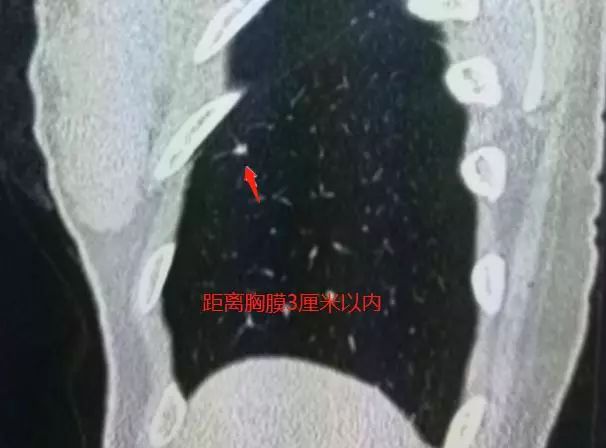

胸膜下小结节,边缘见多发小条索

从CT片上可以看到,这个小结节位于她右肺下叶胸膜下,大约5毫米,形态不规则,边缘有小条索影。

2、正常淋巴结几乎都位于胸膜下,迄今为止所有的报道,均距离胸膜或叶间胸膜小于2.0厘米。

4、边缘常可见到1-5条细线与胸膜、叶间胸膜相连,或注入肺静脉,这是诊断的关键!但必须进行CT扫描观察。